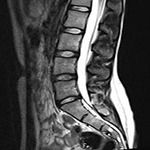

- МРТ пояснично-крестцового отдела позвоночника